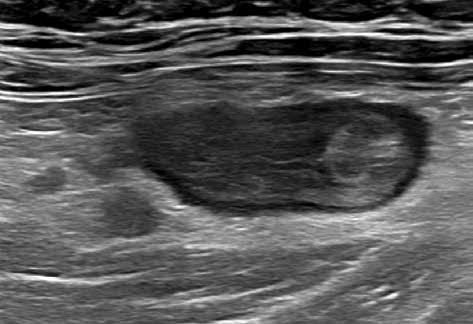

Obr. 1–3: CEUS. Pacient s Crohnovou nemocí ve fázi aktivního zánětu. Po podání kontrastní látky je patrné postupné sycení střevní stěny (1, 2, levá část obrázku), která je výrazně zesílená s akcentovanou hypoechogenní sliznicí (1, 2, pravá část obrázku). Křivka sycení pak svědčí rovněž pro akutní fázi zánětu (3).

Obr. 4–7: Elastografie. U pacienta s Crohnovou nemocí ve fázi aktivního zánětu vidíme edematózní stěnu s prosáknutím a uzlinami v okolí (5). Elastograficky je stěna „měkčí“ (4) ve srovnání s pacientem s chronickou fází onemocnění (6, 7), u kterého je stěna fibrózně změněná.